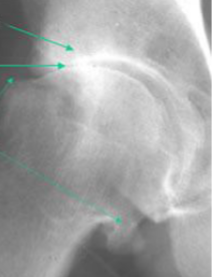

Psoriatic Arthritis

Dactylitis of third & fourth toes

Enthesitis of right Achilles' tendon

Dactylitis of middle finger

Pencil in cup deformity